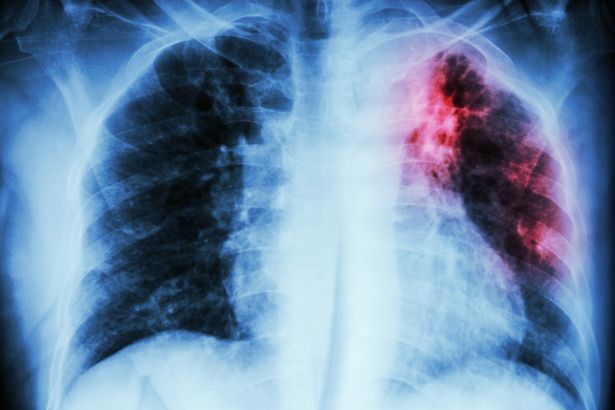

Cases of a Victorian superbug are rising across much of Gloucestershire as medics identify record levels of a worrying drug-resistant strain.

Figures released by the UK Health Security Agency (UKHSA) show there were 5,490 notifications of tuberculosis (TB) in England in 2024.

The proportion of drug-resistant TB reached its highest level since enhanced surveillance began in 2012. Of all laboratory-confirmed cases, 2.2% showed resistance to multiple drugs.

Tuberculosis cases are on the riseTuberculosis cases are on the rise(Image: Getty Images/iStockphoto)